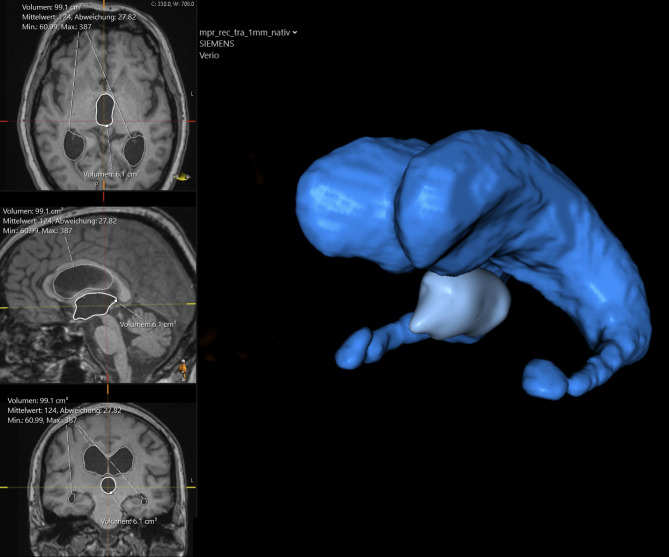

Abstract Image